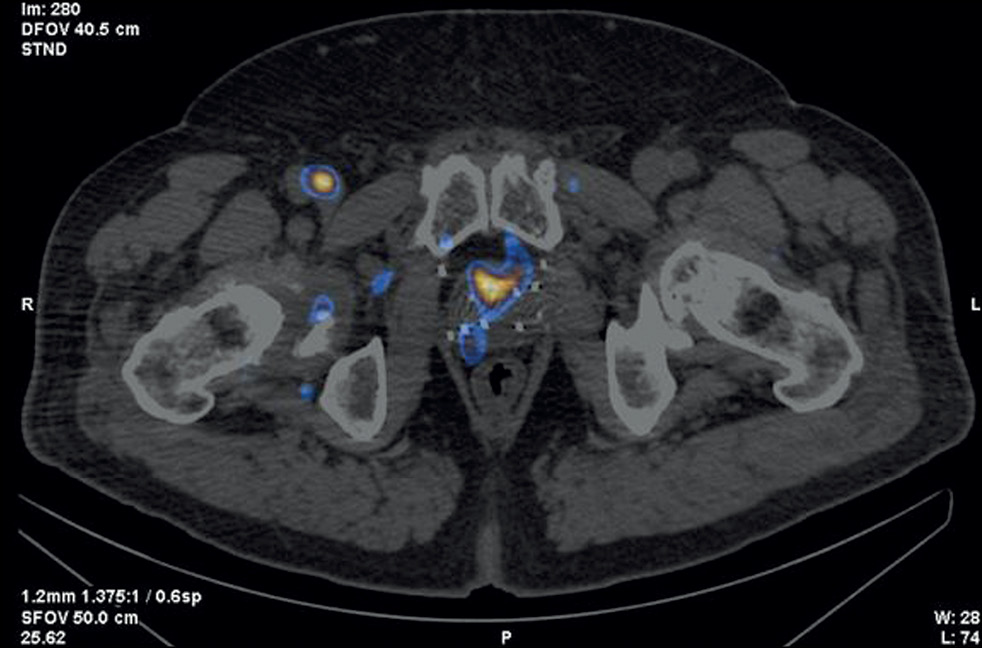

Patient M., 6 years old, had an increased PSA level of 6.8 ng/mL and underwent a multifocal prostate biopsy at a local clinic. The diagnosis was confirmed morphologically as adenocarcinoma, Gleason 6 (3 + 3), based on data from the transitory zone of the right prostate lobe. Adenocarcinoma elements were not found in other prostate biopsy specimens. Considering MRI evidence of changes in the same zone, implantation with 30 125I sources with a 32-cm3 volume was proposed.

SPECT/CT with 99mTc-HYNIC-PSMA revealed diffuse focal RP accumulation under the base of the bladder. PET/CT with 68Ga-PSMA-11 was additionally performed to more accurately visualize prostate lesions. PET/CT revealed multiple sites of RP accumulation in the prostate gland, indicating that the tumor was multifocal (Figure 8). Implantation planning was adjusted to include the total volume of the prostate gland (78 cm3) using 90 125I microsources (instead of preliminary 30 microsources).

Fig. 8. Patient M., 69 years old, PET/CT with 68Ga-PSMA-11: Sites of radiopharmaceutical accumulation in the prostate gland, multifocal tumor.

On February 25, 2022, implantation was performed for the total volume of the prostate gland. The initial prostate volume for brachytherapy was 32 cm3. PET/CT revealed a volume of 72 cm3 for implantation. The PSA level decreased to 0.31 ng/mL within a year after brachytherapy.